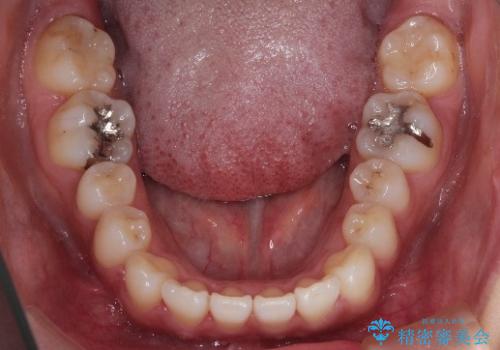

- 前歯の歯並びの改善を希望され来院された患者様です。

初診時の歯並びの状態としては、上下ともに全体に及ぶの中等度のがたつき(叢生)があり、全特に左上の前歯は1本だけ引っ込んでいる状態でした。

抜歯は行わず上顎の奥のスペースを利用して歯をスライドする方法の他に歯列弓の拡大やディスキング(歯と歯の間の隙間を作る処置)を行い叢生を改善しました。

歯の大きさの不揃いが原因の正中のズレは、ディスキング量を調整することで合わせました。